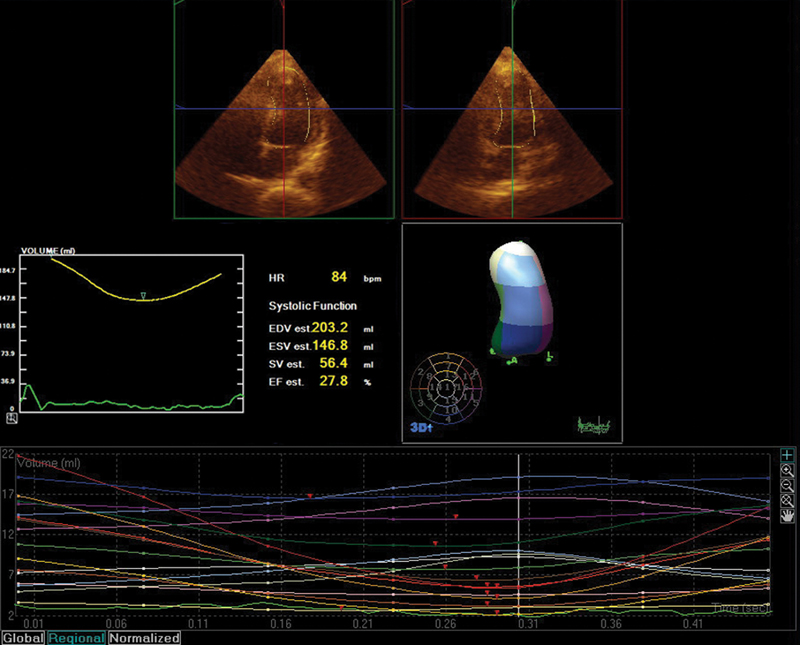

فحوصات تشخيصية لبعض امراض القلب والشرايين التاجية